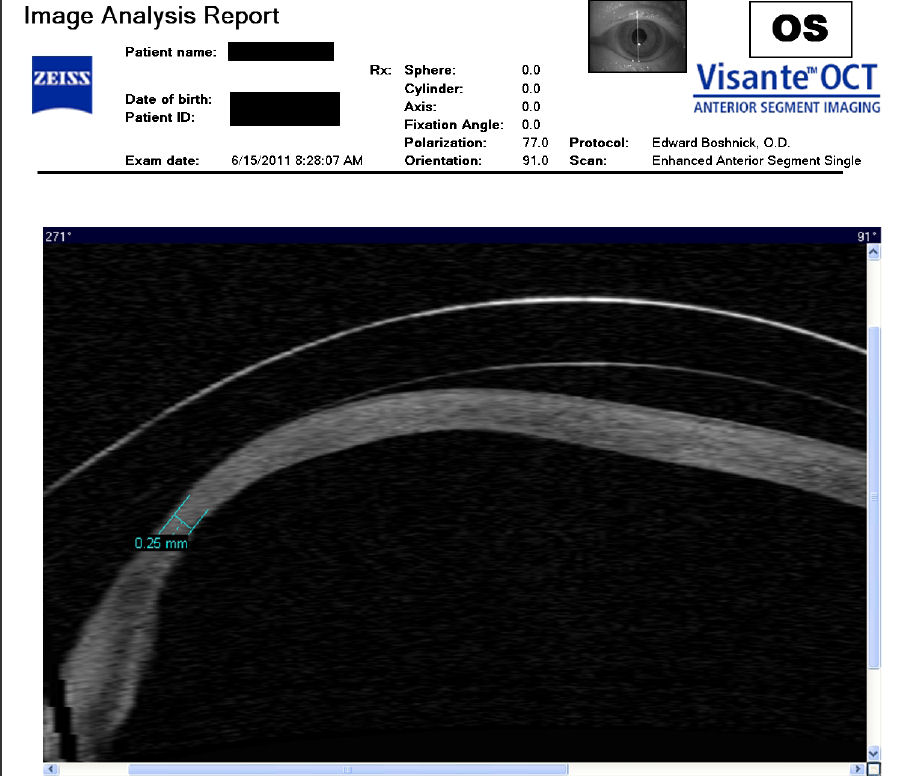

Следующие изображения были получены с использованием метода, называемого оптической когерентной томографией, или ОКТ. Прибор позволяет получить изображение в поперечном сечении путем сканирования передней части глаза (переднего сегмента) лучом света. Думайте об этом как об ультразвуке, использующем свет вместо звуковых волн для создания изображения живых тканей.

На изображении, приведенном непосредственно ниже, представлен снимок здоровой, неоперированной роговицы для сравнения со следующими изображениями эктатических роговиц после операции LASIK.

На снимке ниже показана эктазия роговицы после операции LASIK. Толщина роговицы в самом тонком месте составляет всего 250 микрон, что в два раза меньше толщины нормальной роговицы. Пациент носит большие терапевтические контактные линзы. Белая изогнутая линия вверху обозначает переднюю поверхность хрусталика. Ниже расположена более слабая белая изогнутая линия, обозначающая заднюю поверхность хрусталика. Между хрусталиком и роговицей находится пространство, заполненное физиологическим раствором, который имеет зернистый вид. Нажмите на изображение, чтобы увеличить его.

На изображении ниже представлен снимок роговицы в поперечном сечении после операции LASIK. Белая изогнутая линия вверху - это передняя поверхность твердой контактной линзы. Следующая едва заметная белая линия - это задняя поверхность линзы. Следующая область, которая имеет зернистый вид, - это пространство между хрусталиком и роговицей, заполненное физиологическим раствором. Роговица имеет классические признаки эктазии - истончение, выпуклость и неправильную форму.

Изображения любезно предоставлены доктором Эдвардом Бошником, который посвятил свою практику восстановлению качественного зрения и информации о эктазия после операции LASIK .